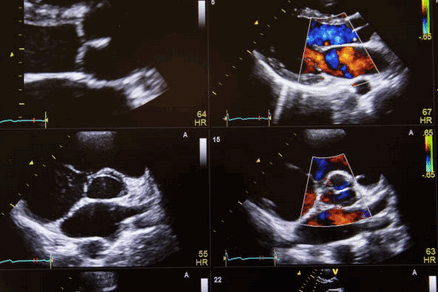

ЭКГ при стенозе устья легочной артерии выявляет признаки перегрузки правого желудочка, отклонение ЭОС вправо. При помощи эхокардиографии обнаруживается дилатация правого желудочка, постстенотическое расширение легочной артерии; допплерография позволяет выявить и определить разницу давления между правым желудочком и легочным стволом.

С помощью УЗИ сердца непосредственно определяются все анатомические компоненты тетрады Фалло: степень легочного стеноза, величина смещения аорты, размер ДМЖП и выраженность гипертрофии правого желудочка.

Эхокардиография при стенозе легочной артерии

Стеноз легочной артерии является наиболее часто встречающимся пороком развития сердца, который хорошо можно определить на эхокардиографии. Согласно статистике, этот порок вместе с атрезией легочной артерии составляет почти половину всех случаев врожденных пороков сердца. При этом сушение легочной артерии встречается по крайней мере в пять раз чаще, чем полная атрезия. Расположение, размеры и степень стеноза на эхокардиографии бывают разными. По данным эхокардиографии описываются следующие главные типы:

- Сужение инфундибулярной части правого желудочка мышечной пластинкой или фиброзным тяжем (так называемый инфундибулярный стеноз). В некоторых случаях гипертрофическая мышечная или соединительная ткань, создающая впечатление рубца, суживает большую часть инфундибулярного отдела сердца, так что он меняется на эхокардиографии в узкий канал разной длины. Только в редких случаях отмечается стеноз на всем протяжении инфундибулярного отдела. В большинстве случаев инфундибулярный отдел сохраняет коническую форму. С самого начала он постепенно сужается, так что его просвет уменьшается непосредственно под устьем легочной артерии, образуя небольшое отверстие (подклапанный инфундибулярный стеноз). Иногда через гипертрофированную мышечную ткань инфундибулярного отдела проходит несколько узких извитых канальцев неправильной формы, которые открываются в правый желудочек и соединяются друг с другом по направлению к устью легочной артерии. Гораздо чаще сужение распространяется на небольшую часть инфундибулярного отдела, либо в самом его начале (прединфундибулярный стеноз, или стеноз инфундибулярного устья), либо на любое место инфундибулярного отдела, начиная от его устья, вплоть до его конца, непосредственно под клапанами (инфундибулярный стеноз в прямом смысле слова, который может быть высоким, промежуточным или низким). В таком случае инфундибулярный отдел над местом сужения на эхокардиографии бывает расширенным и образует как бы добавочный третий желудочек, величина которого зависит от места сужения. Он достигает наибольших размеров при прединфундибулярном и при низком инфундибулярном стенозе. Таким образом возникает значительное выпячивание части инфундибулярного отдела в вентральном направлении, хорошо заметное эхокардиографическом исследовании. Стенка расширенной части инфундибулярного отдела между местом сужения и устьем легочной артерии может быть утолщенной, состоящей из мышечной ткани, либо утонченной, состоящей из фиброзной ткани.

- Сужение устья легочной артерии на уровне клапанов (клапанный стеноз), возникает в результате слияния створок клапанов, которые в различной мере срастаются своими свободными краями. При максимальном сращении образуется перепончатая перегородка в виде диафрагмы с небольшим закругленным или овальным отверстием, или с поперечной щелью, расположенными в центре диафрагмы или ближе к ее краю. Эта перегородка иногда бывает тонкостенной, нежной и податливой, в других же случаях утолщенной, фиброзной или даже обызвествленной, что можно определить на эхокардиографии. В большинстве случаев перепончатая перегородка со временем вдавливается под влиянием тока крови в легочную артерию в виде воронки или соска грудной железы с небольшим устьем на вершине, расположенным в центре или эксцентрично, причем устье выступает в легочную артерию в виде рыбьего рта. Некоторые авторы считают, что стеноз этого типа возникает в результате внутриутробного воспаления. Доказательство такого образования стеноза является затруднительным. Воспалительное происхождение возможно скорее всего предполагать при чистом стенозе и пульмональной клапанной атрезии или при клапанном стенозе и атрезии легочной артерии, сочетающейся со стенозом и атрезией правого венозного устья.

- Стеноз самого устья, то есть стеноз клапанного кольца, встречающийся на эхокардиографии в редких случаях в качестве изолированного порока, как правило, сопровождает тяжелые изменения инфундибулярного отдела. Может наблюдаться гипоплазия всего клапанного аппарата. Створки клапанов могут быть свободными или спаянными с образованием диафрагмы. Сравнительно часто встречается образование только двух полулунных клапанов, которые могут быть утолщенными и таким образом способствовать сужению правого артериального устья. Часто у одного и того же больного наблюдается стеноз инфундибулярного отдела, устья и клапанов легочной артерии.

На эхокардиографии ствол легочной артерии по сравнению с аортой бывает в подавляющем большинстве случаев уже, иногда по всей длине, или только в некоторых местах, в то время как остальные части могут быть расширенными. Только в редких случаях он бывает нормальных размеров. Ширина ветвей чаще всего пропорциональна ширине ствола, однако в некоторых случаях даже при значительной гипоплазии ствола обе ветви могут быть развиты нормально. Ширина обеих ветвей легочной артерии может быть весьма разной.